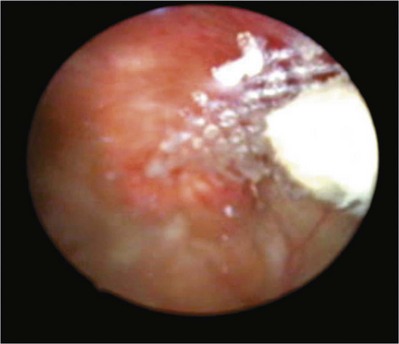

Erosion of an autologous PVS is rare. There are only four cases of erosions documented in peer-reviewed literature. Handa and Stone (1999) and Golomb and colleagues (2001) reported on an individual case of an autologous sling eroding through the midurethra. Possible causative factors include misplacement or incorrect technique in sling passage or positioning, excessive tension, or traumatic urethral instrumentation after placement of a PVS (i.e., for retention, hematuria clot evacuation, surveillance cystoscopy). In both cases the eroded portion of the sling was excised and the urethra was closed (Handa and Stone, 1999; Golomb et al, 2001). Clemens and colleagues (2000) described two cases of bladder dome erosion by an autologous rectus fascial sling that presented as recurrent UTI, dysuria, and UUI. One of these patients presented with a bladder calculus on sling material that was visible on cystoscopy. The other woman presented with edema and suture at the dome. In both cases adequate cystoscopy with 30- and 70-degree lenses after Stamey needle passage may have avoided this. Both cases were successfully managed with endoscopic removal of stitches and treatment of the bladder stone. No further treatments were necessary (Clemens et al, 2000).